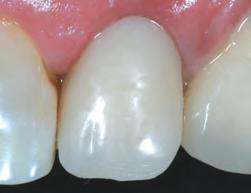

1. Well-healed tissue 2 weeks post-op.